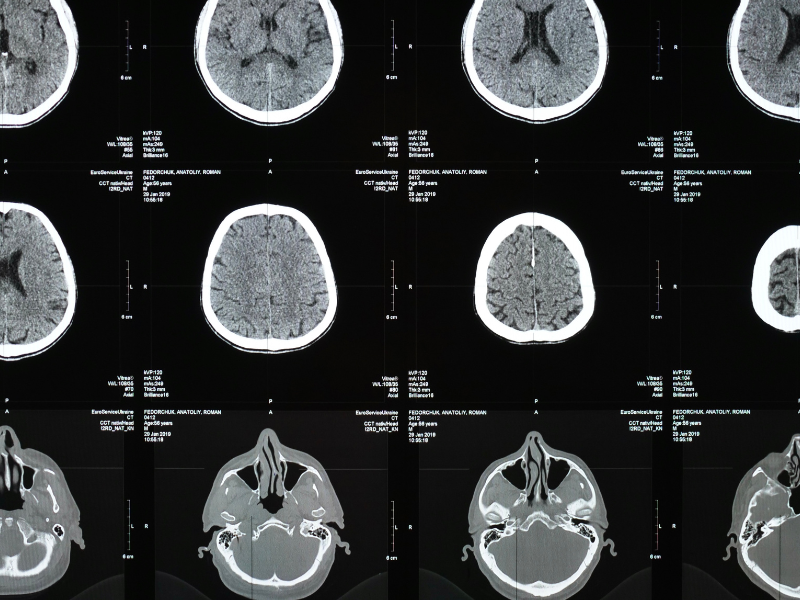

Diagnosis for hypopituitarism involves blood tests to check hormone levels, followed by stimulation tests and imaging studies like MRI to assess the pituitary gland.